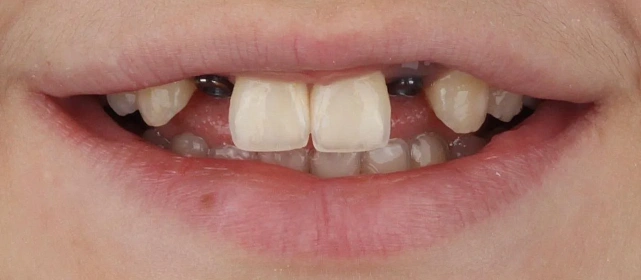

Прозрачные элайнеры 3D Smile на обе челюсти. Выровнять зубы и нормализовать смыкание. Срок — около 2 лет.

Лечение заняло 4 года (март 2022 — март 2026). Капы менялись каждые 1–2 недели, визиты к ортодонту для контроля прогресса и выдачи новых наборов.

Решение: Поставили элайнеры 3D Smile на обе челюсти. Лечение заняло 4 года и потребовало нескольких последовательных этапов коррекции. Капы менялись каждые 1–2 недели, на контрольных визитах отслеживали прогресс и выдавали новые наборы. Зубы встали в правильное положение, смыкание нормализовалось. Зафиксировали ретейнеры на обе челюсти, изготовили ретенционные капы. Пациентка прошла онлайн-консультацию с ортопедом для оценки дальнейших шагов.